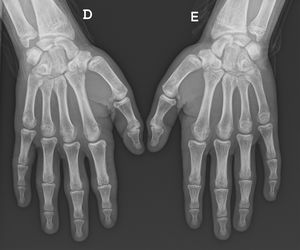

Niño de 14 años previamente sano, que presentó hinchazón indolora circunscrita a las articulaciones de la mano derecha de un año de duración. Sin antecedentes personales o familiares de interés. El examen físico reveló engrosamiento cutáneo sobre las articulaciones interfalángicas proximales y metacarpofalángicas (fig. 1). No había ningún otro signo inflamatorio. La evaluación de la fuerza muscular fue normal. En el momento de la consulta, el paciente practicaba judo y culturismo sin ninguna limitación. Informó que el inicio de las lesiones se asoció con un aumento en el uso de la PlayStation®. Los resultados de la analítica, incluyendo la velocidad de sedimentación globular y la proteína C reactiva, fueron normales, como lo fueron las radiografías de ambas manos (fig. 2). Se derivó al paciente a dermatología para descartar otras posibles condiciones. Se inició tratamiento con masajes localizados con un emoliente y reduciendo el uso de la PlayStation®. El paciente fue reevaluado cada año, observándose una mejoría progresiva de las lesiones.